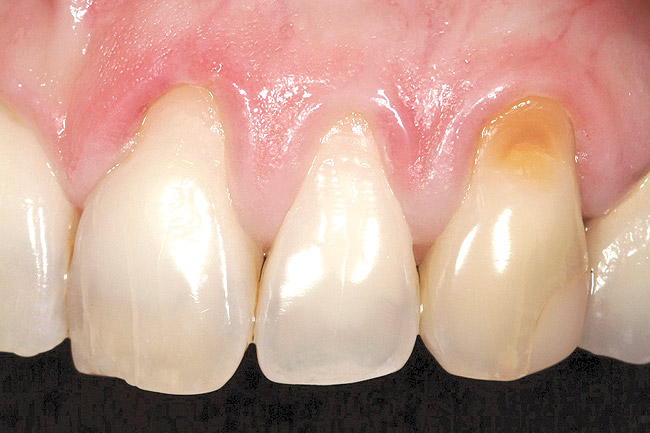

Figure 16  Case Two Preoperative clinical view, maxillary left central incisor.

Figure 16

A 27-year-old non-smoking man presented for esthetic enhancement of the left central incisor, which had a pre-existing full-coverage restoration that required replacement (Figure 16). The patient had begun orthodontic treatment in the mandibular arch to correct a minor occlusal imbalance and required coronal repositioning and soft tissue grafting to correct gingival recession at the facial of the right canine, in addition to correction of the free gingival margin at the facial of the left central incisor, which was asymmetrical to the free gingival margin of tooth No. 8. Additionally, the facial gingival tissues were of a thin biotype, which at the facial surface of the left central incisor allowed for the darkened root surface to be visible through the tissue (Figure 16).

The treatment plan was to accomplish an increased zone of keratinized tissue at tooth No. 6, and increase the thickness of the facial tissue at tooth No. 9, in addition to coronally repositioning the free gingival margin. Complicating this treatment plan was the fact that at the facial surface of tooth No. 9, a biologic width invasion was present due to the prepared margin for the pre-existing restoration being placed too close to the facial alveolar crest of bone (the patient had presented to the periodontist with a provisional restoration in place). Any correction to the area would require movement of the facial margin of the tooth in a coronal fashion to re-establish the appropriate distance from the facial height of bone to the margin of the restoration. Additionally, options were given to the patient for harvesting the soft tissue, using connective tissue from the palate, or the use of an acellular dermal matrix graft, which would nullify harvesting tissue from the palate region.